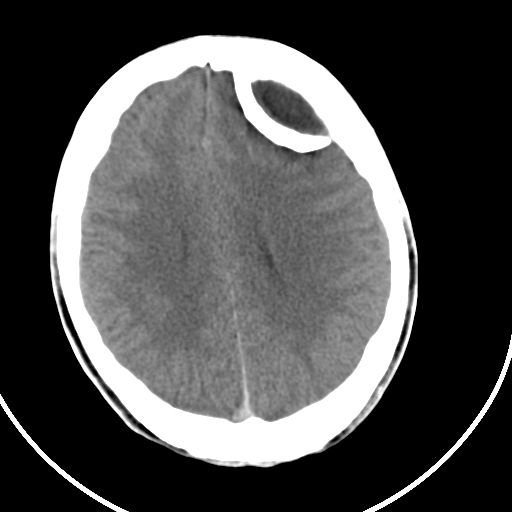

标题: CT21939:男20岁,外伤一年后,现头疼. [打印本页]

标题: CT21939:男20岁,外伤一年后,现头疼.

左侧额部硬膜外血肿机化、骨化。

左侧额部硬膜外血肿机化、骨化